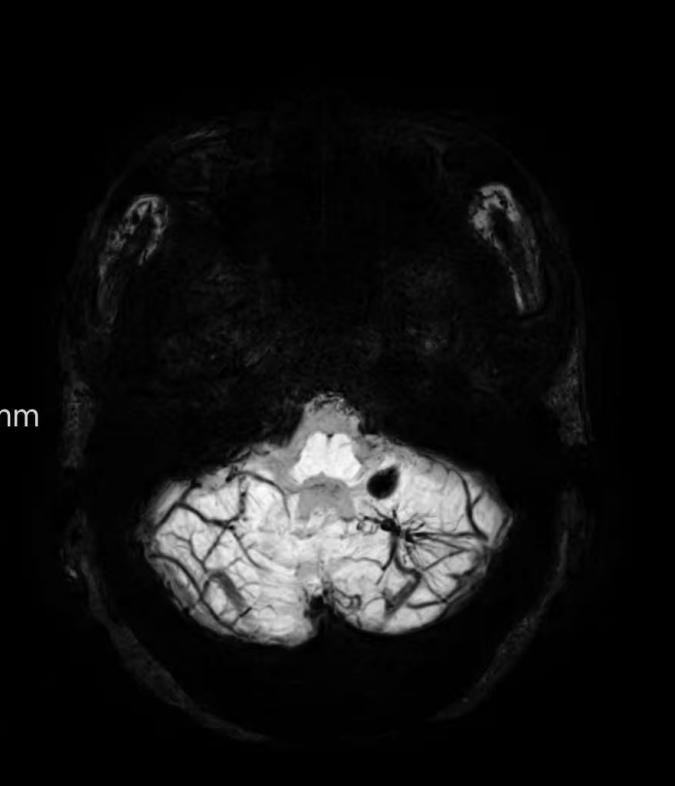

臨床中遇到一位患者,中年女性,反復(fù)出現(xiàn)頭痛,時(shí)輕時(shí)重,常規(guī)CT及磁共振檢查無(wú)明顯異常發(fā)現(xiàn),最后建議加做一個(gè)磁共振磁敏感加權(quán)成像(SWI),結(jié)果發(fā)現(xiàn)是左側(cè)小腦發(fā)育性靜脈畸形(DVA),SWI清晰顯示畸形的靜脈及周圍含鐵血黃素沉積;如下圖。這正是她頭痛的原因。

①診斷靜脈畸形:SWI能高精度地顯示發(fā)育性靜脈畸形——一種常見的腦血管畸形。在SWI上,發(fā)育性靜脈畸形會(huì)呈現(xiàn)典型的“海蛇頭”或“水母頭”征,即一堆細(xì)小的髓靜脈匯入一支粗大的引流靜脈。